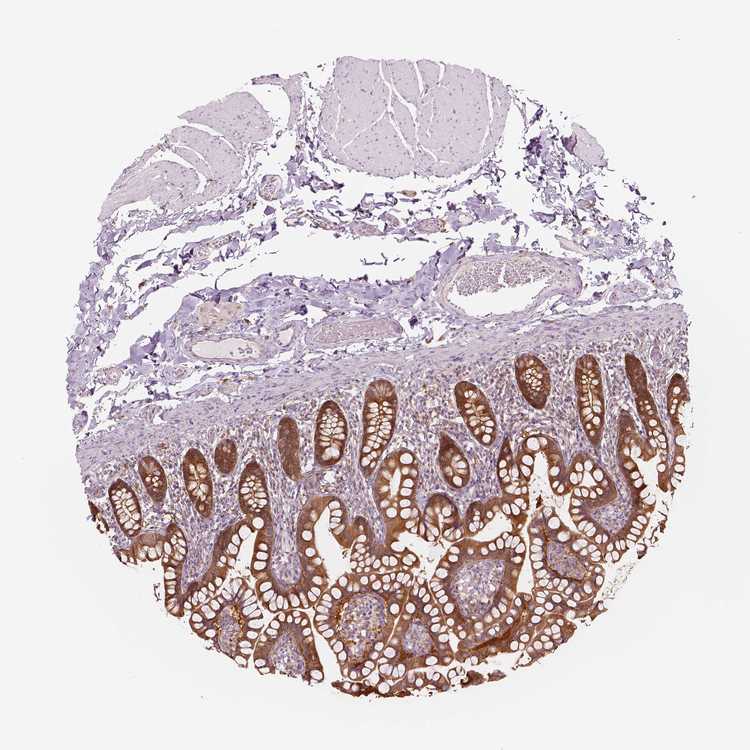

TISSUE PRIMARY DATA SMALL INTESTINE Show tissue menu

SMALL INTESTINE - Antibody stainingi

Antibody staining in the annotated cell types in the current human tissue is reported as not detected, low, medium, or high, based on conventional immunohistochemistry profiling in selected tissues. This score is based on the combination of the staining intensity and fraction of stained cells.

Each image is clickable and will lead to virtual microscopy that enables deeper exploration of all samples and also displays staining intensity scores, fraction scores and subcellular localization as well as patient and tissue information for each sample.

Antibody HPA023314Antibody HPA078682

Glandular cells HighHigh